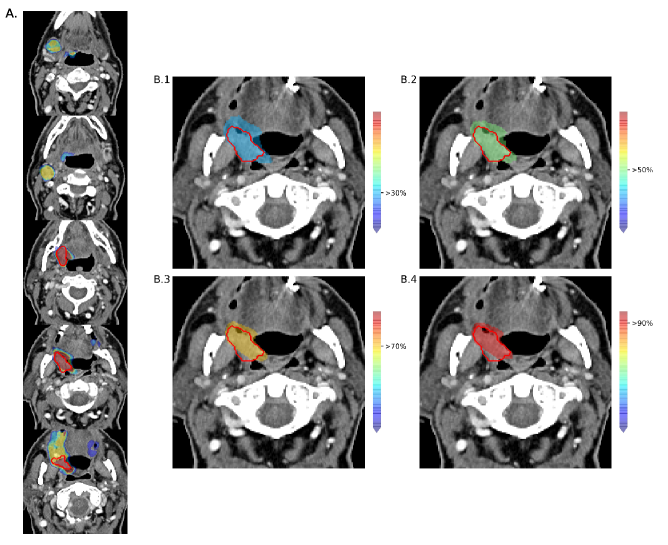

3.4 Qualitative results

In figure 3, we show how the probability map predictions of our network looks on the CT image of a patient. On the left side, the total range of probability is shown on few slices extracted from the axial plane. On the right side, four cases of different probability threshold settings are displayed. The range of probability shown on the image for each case corresponds to the one above the selected threshold up to 100%. Increasing the probability percentage shrinks the predicted area around the tumor.